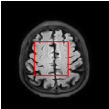

Figure 5 provides the qualitative comparison of the various methods on the four datasets at a scale of 4. The top, second, third, and bottom rows are the SR results under the FastMRI, clinical brain, clinical tumor and clinical pelvic datasets, respectively. The red boxes indicate the zoom-in region of complicated anatomical structures along with their corresponding error maps. Note that the brighter textures in the error maps, the lower the quality of the reconstructed images. As can be seen, compared to methods based on Transformers and CNNs, diffusion-based methods like DisC-Diff and DiffMSR (Ours) are capable of reconstructing high-realistic images with promising reconstruction metric scores (PSNR and SSIM). Nevertheless, while DisC-Diff can reconstruct high-precision MR images, it does not preserve the structure present in the original HR images, introducing some additional information that can affect medical diagnosis. In contrast, our method combines DM and PLWformer, which can preserve the original image’s structure while restoring high-frequency information.

In this section, we present more visual qualitative comparisons. Figures 8, 9, 10, and 11 show the reconstruction results of each method in FastMRI, clinical brain, clinical tumor, and clinical pelvic, respectively. As can be seen, although DisC-Diff can reconstruct MR images with high-frequency information, it fails to preserve the structure and content of the original Target HR image effectively, resulting in image distortion. In contrast, our proposed DiffMSR can restore high-frequency information while preserving the structure of the original HR image, indicating the effectiveness of the joint use of DM and PLWformer.